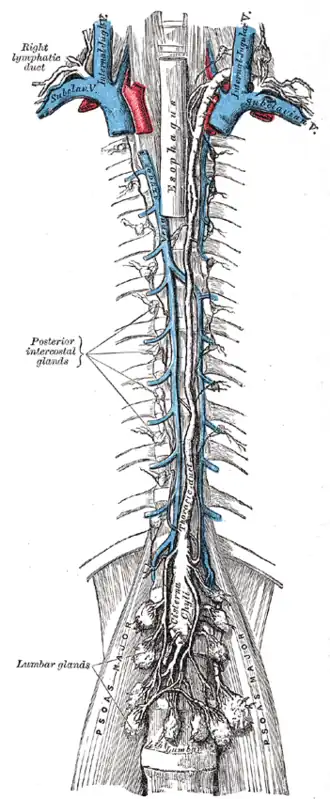

Position schématique des nœuds lymphatiques primaires. Nœuds et vaisseaux lymphatiques profond du tronc.

Nœuds et vaisseaux lymphatiques profond du tronc. Système lymphatique abdominal et thoracique.